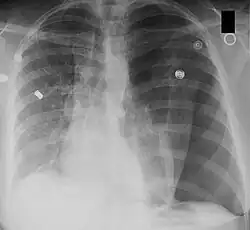

Mediastinalshift

Ein Mediastinalshift oder eine Mediastinalverlagerung bezeichnet die Verschiebung des Mediastinums aus der Mittellinie des Thorax nach links oder rechts. Der Begriff wird in der Röntgendiagnostik verwendet.

Ursächlich ist entweder eine Verminderung des Volumens der Thoraxhälfte auf der Seite, zu der das Mediastinum verlagert ist, oder eine Vermehrung des Volumens auf der anderen Seite.